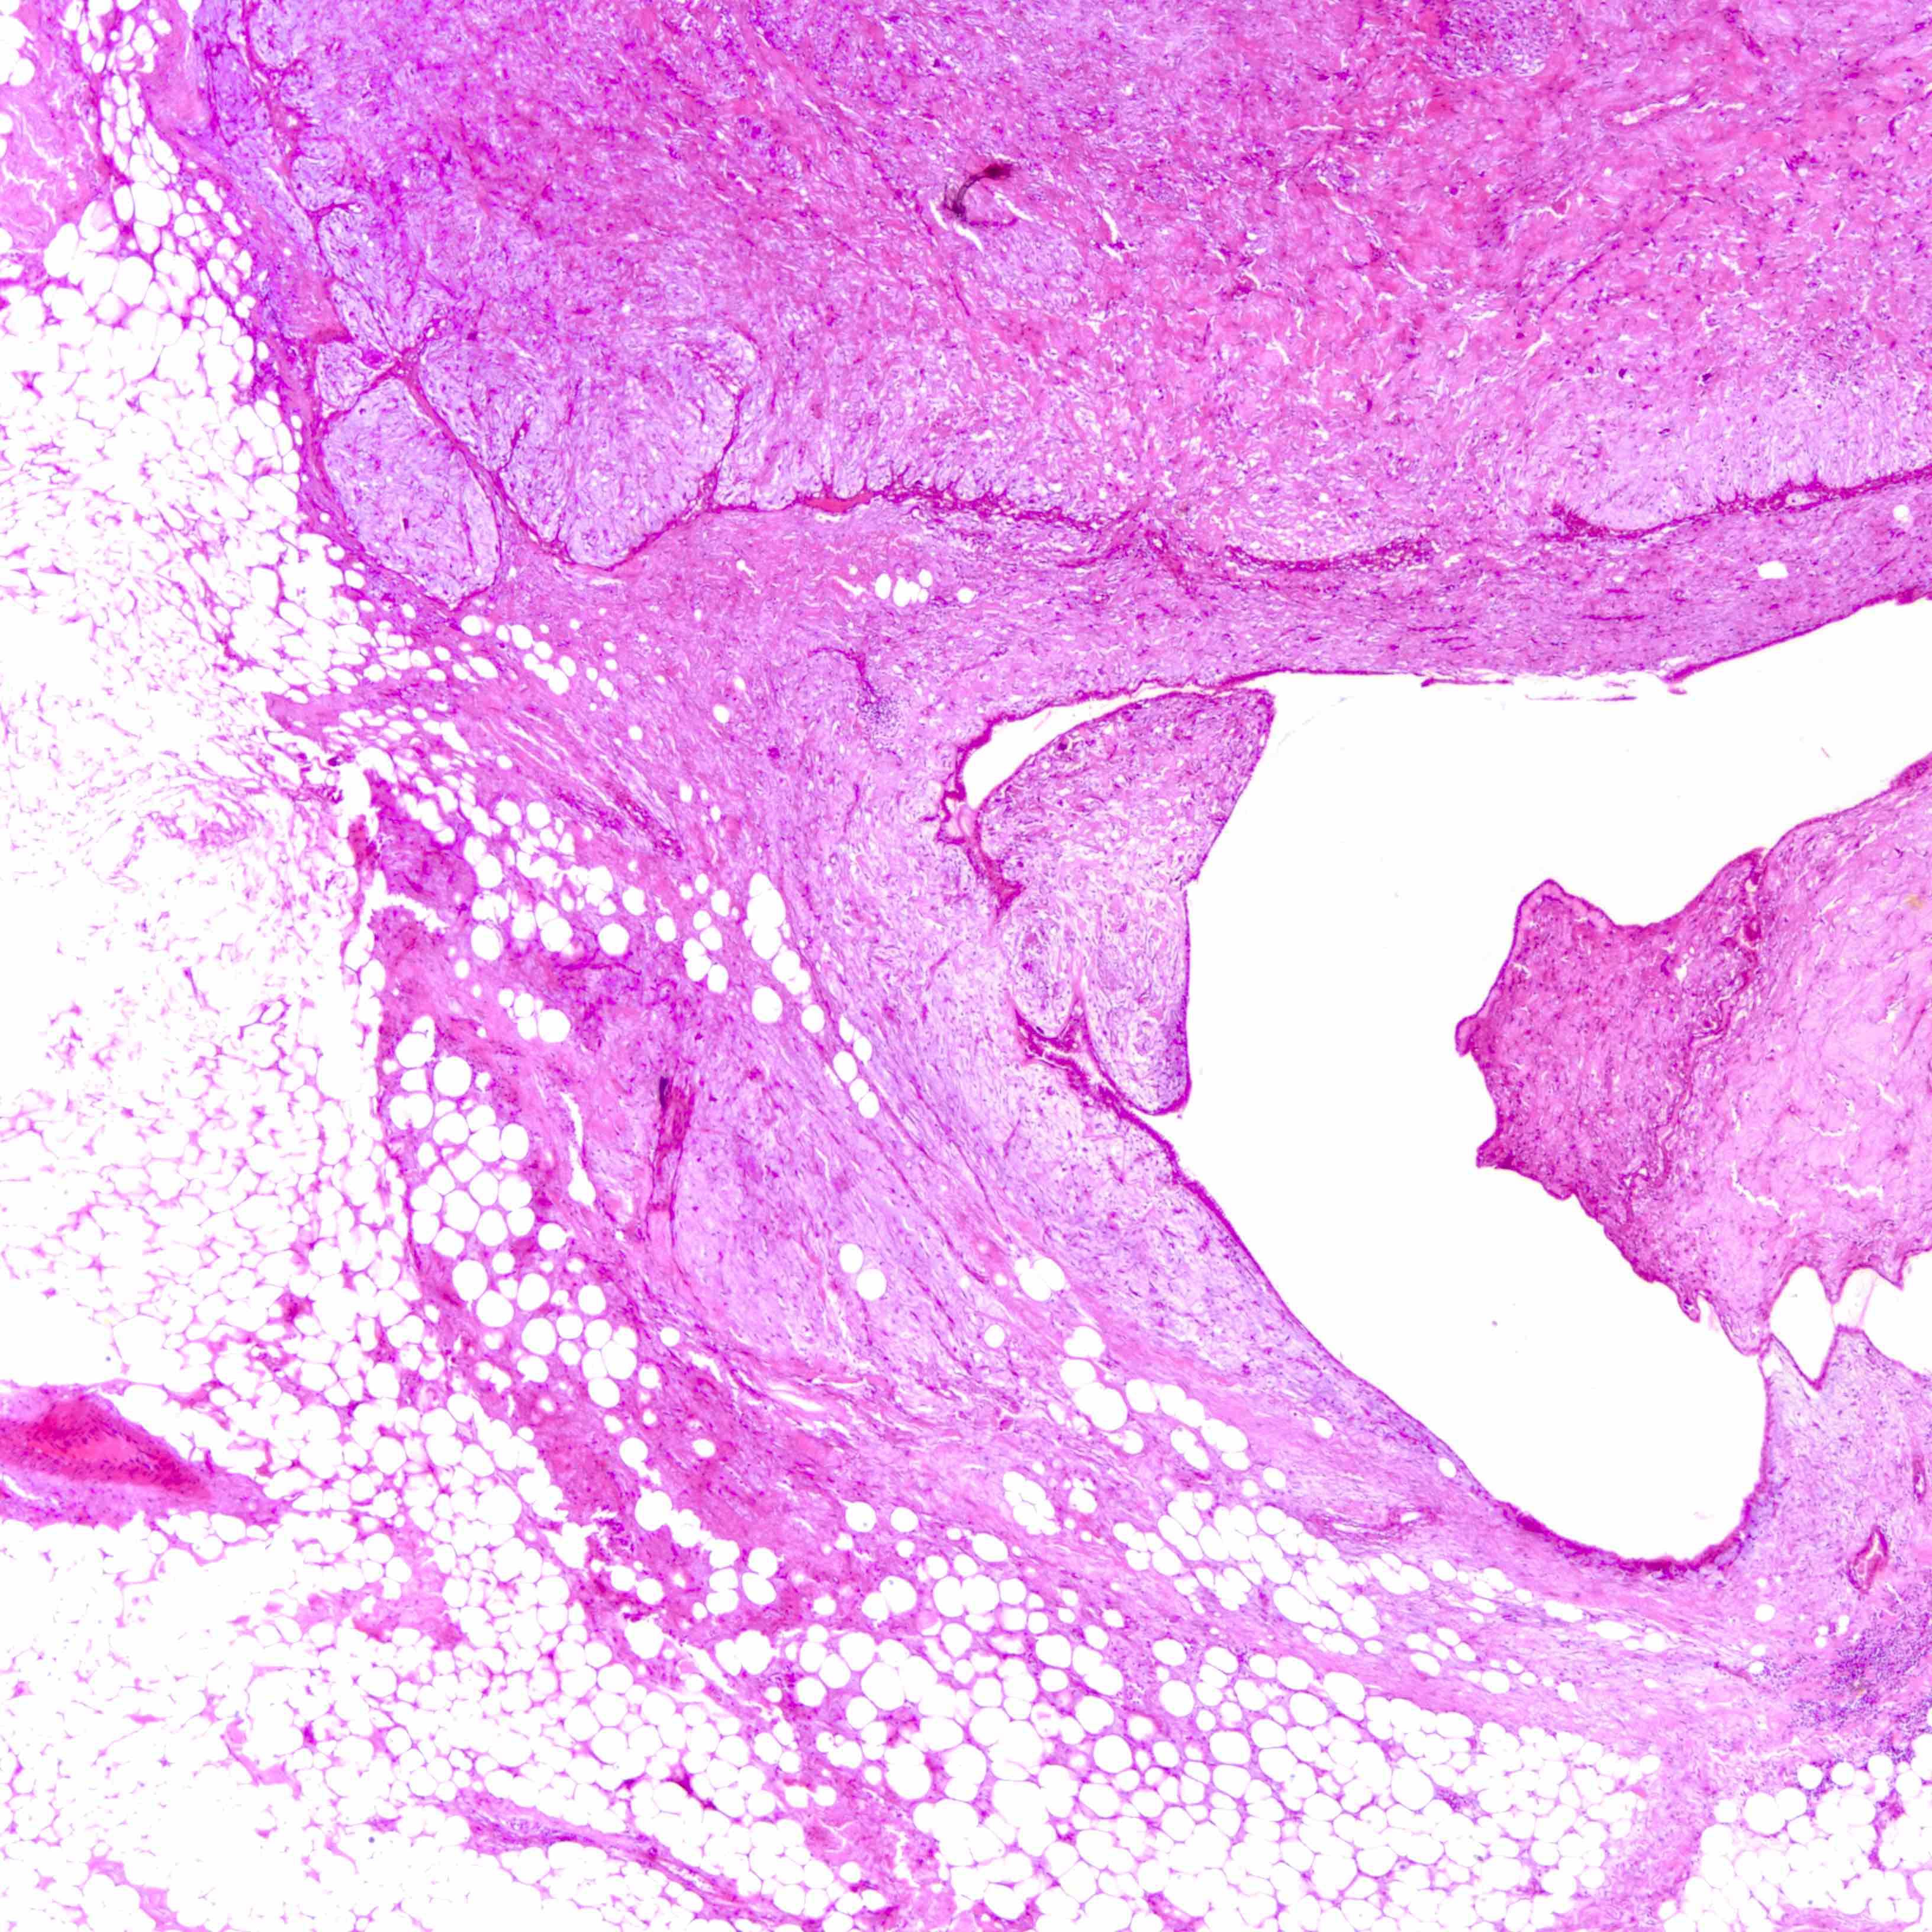

Microscopic (histologic) images

Contributed by Joshua J.X. Li, M.B.Ch.B. and Gary M. Tse, M.B.B.S.

Borderline phyllodes tumor